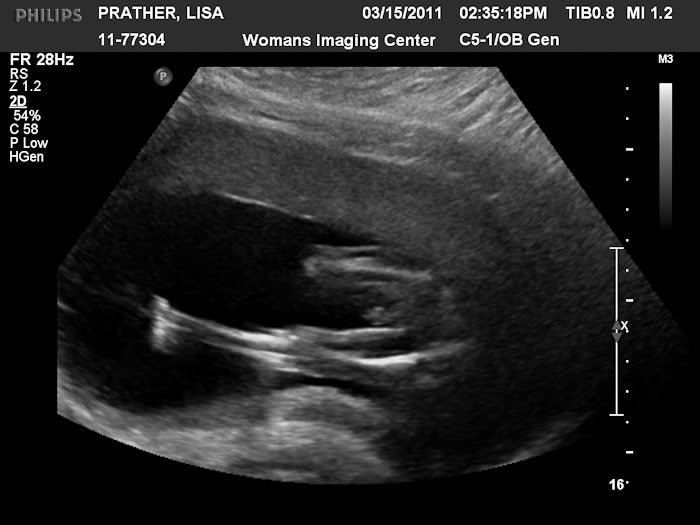

Today is our big ultrasound so I thought for today's throwback Thursday I would post Stephen's ultrasound pictures.  I was 20 weeks pregnant here.  This is the day we found out we were having a boy.

photo 011_web.jpg